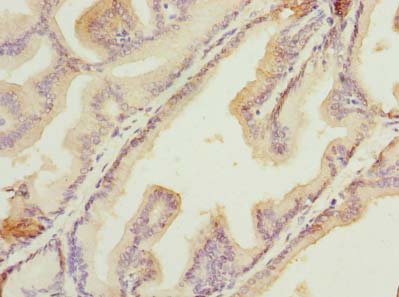

ApplicationELISA, WB, IHC; Recommended dilution: WB:1:500-1:2000, IHC:1:20-1:200